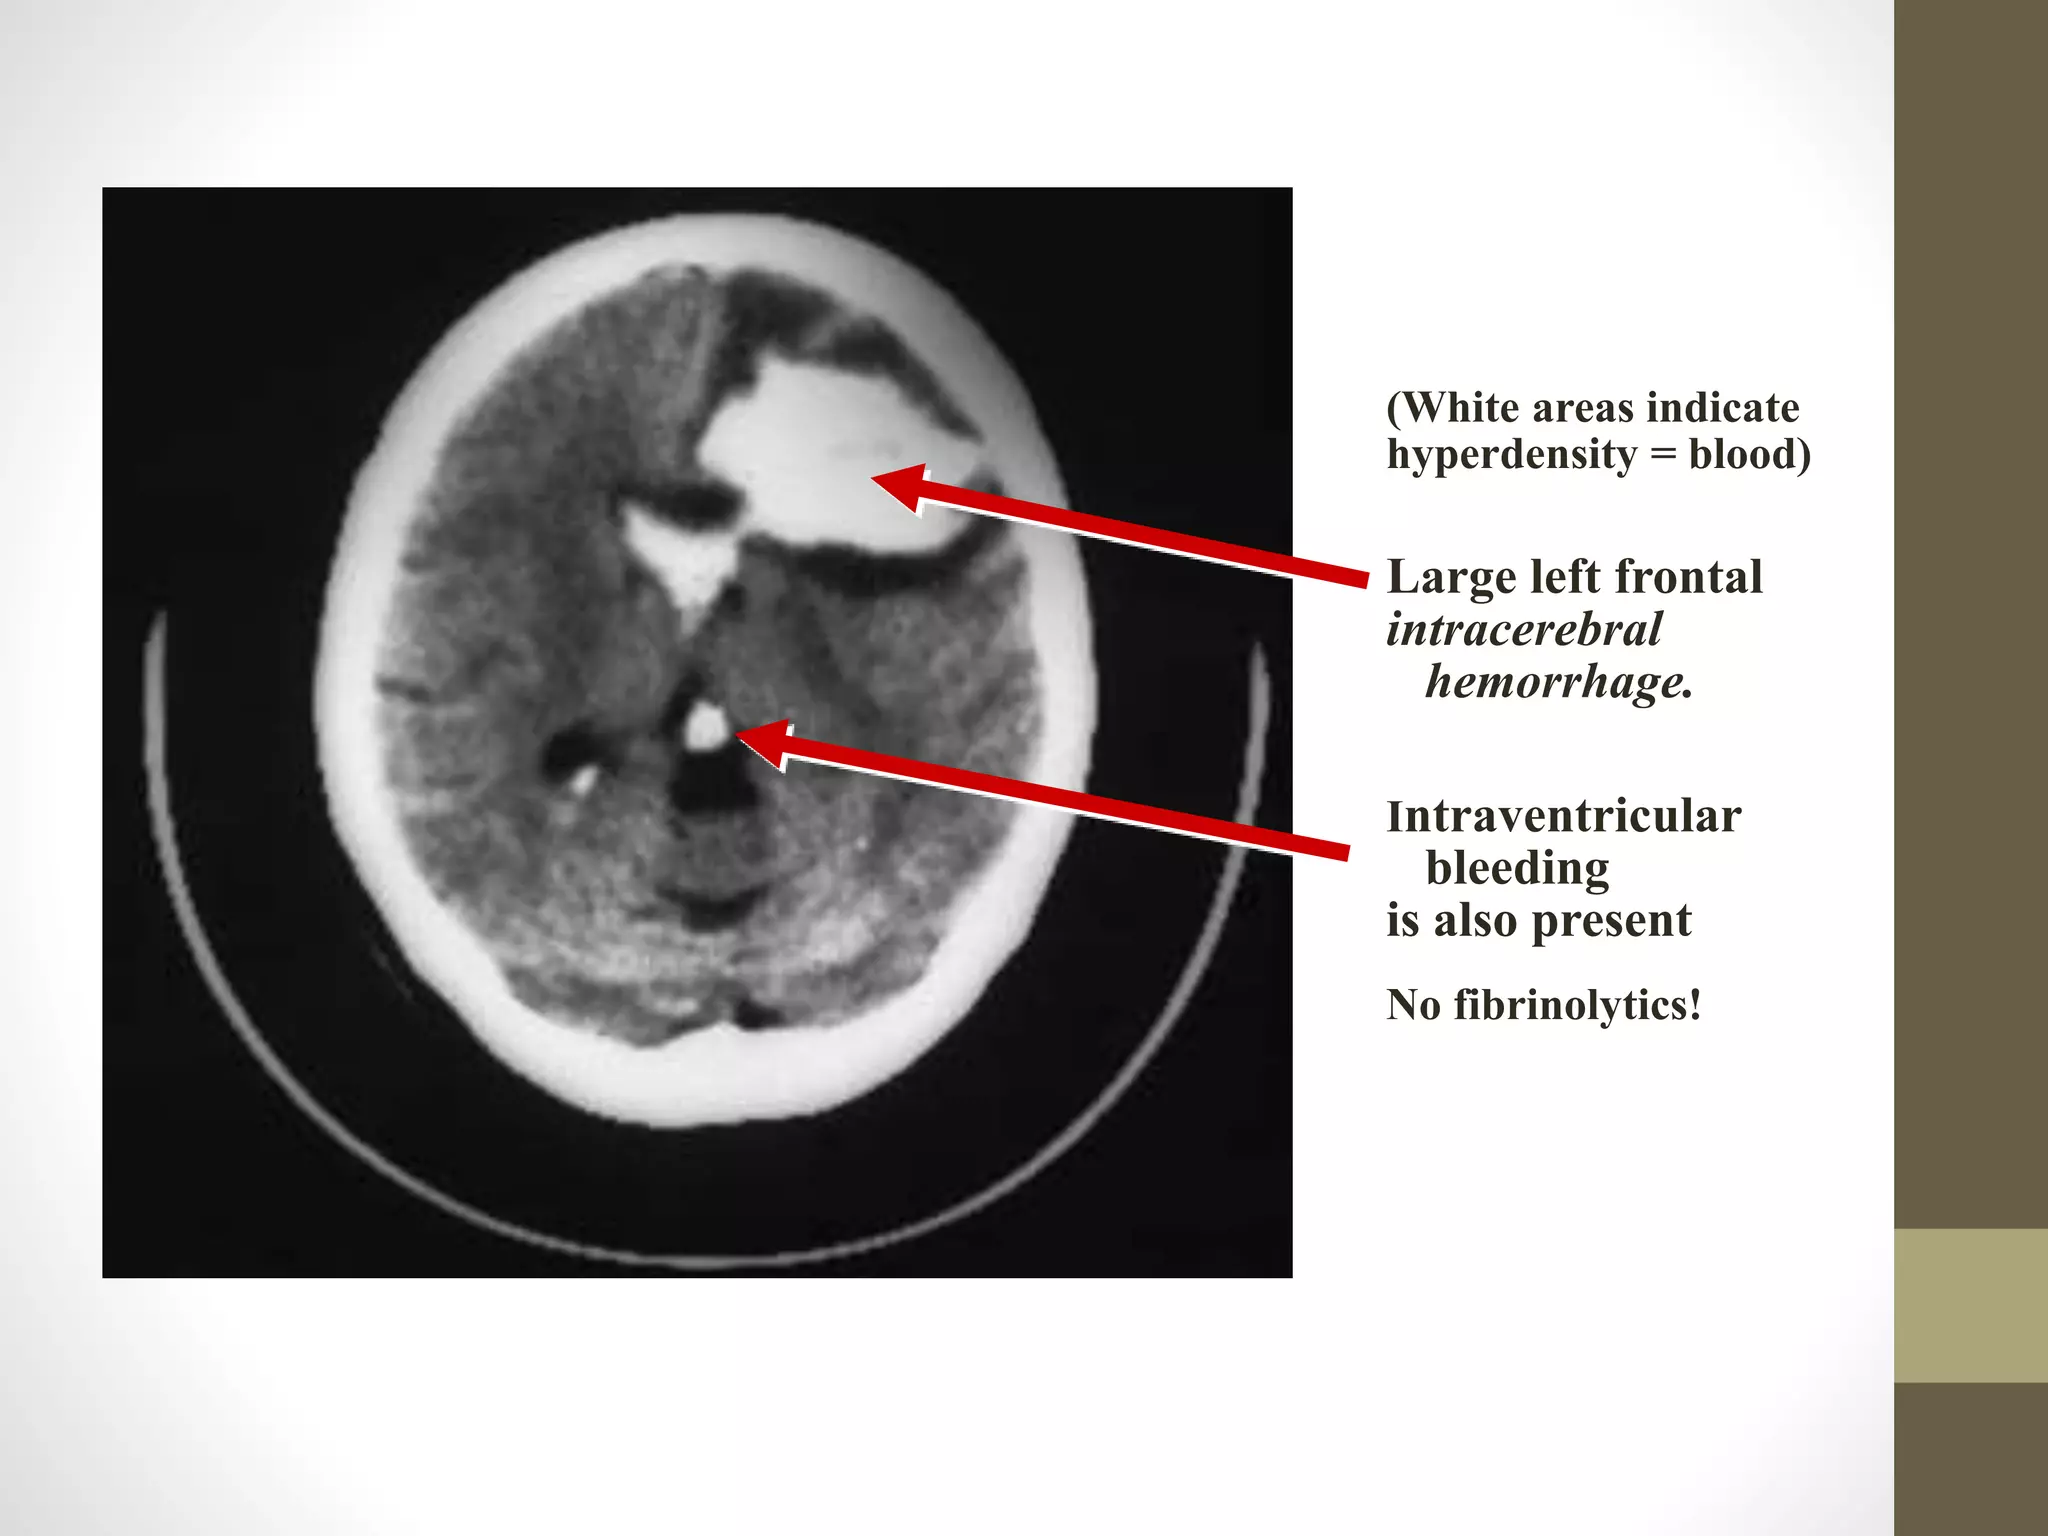

(White areas indicate

hyperdensity = blood)

Large left frontal

intracerebral

hemorrhage.

Intraventricular

bleeding

is also present

No fibrinolytics!

(White areas indicate hyperdensity= blood) Large left frontal intracerebral hemorrhage. Intraventricular bleeding is also present No fibrinolytics!